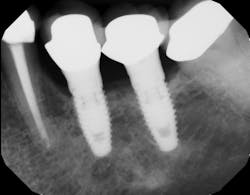

Upon clinical examination, a 10 mm probing with suppuration was noted. Radiographs showed no bone loss, so the lesion was diagnosed as severe mucositis (figure 1). However, upon surgical entry, bone loss was noted.